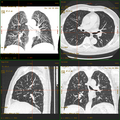

Kombination aus multiplanarer Reformatierung und sliding thin slab. Der Bildkursor befindet sich in der Harnblase. Die Originalschichtdicke beträgt 1,25 mm, dargestellt wird in allen Ansichten gemittelt (= average) in 3,7 mm bzw. 3,8 mm Dicke. -

Kombination aus multiplanarer Reformatierung und sliding thin slab. Der Bildkursor befindet sich im rechten Lungenflügel. Die sts-Bildstapel werden in Form von MIP-Darstellungen gezeigt (STS-MIP).[52] Links oben befindet sich eine VR-Darstellung der Lunge; sie zeigt einen Blick auf die koronal an Kursorposition geschnittene Lunge. -